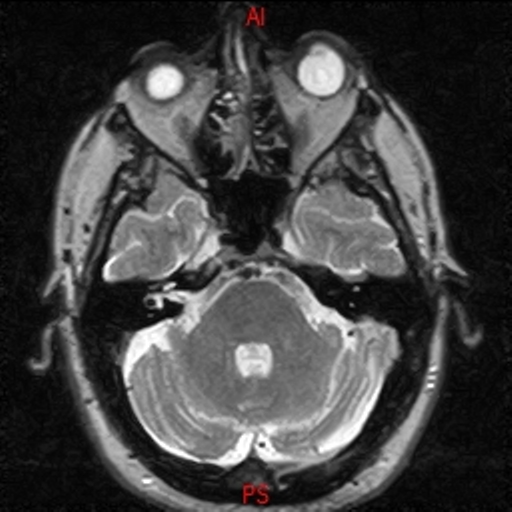

• RESONANCIA NORMAL CRANEAL T2 AXIAL